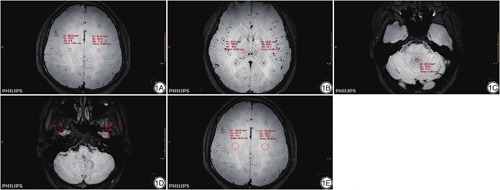

在轴位上进行感兴趣区(region of interest, ROI)勾画测量(图1),为保证ROI大小形状一致,采用复制-粘贴ROI的方式进行勾画。SI测量:SI脑白质将ROI放置在半卵圆中心,SI脑灰质将ROI放置在背侧丘脑,SI脑脊液将ROI放置在第四脑室,SI颞肌将ROI放置在颞肌最大层面,四者的ROI面积均为20 mm2;SD背景测量:以脑白质为背景,将面积为100 mm2的ROI放置在半卵圆中心。以上除第四脑室测量两次取平均值外,其余组织均左右两侧对称测量并取平均值。由于使用并行采集技术得到的图像的噪声分布是非均匀的,故没有直接测量背景中空气的噪声,而以脑白质的信号的标准差作为背景噪声[13]。计算CNR时以颞肌信号作为对照,计算公式为:SNR组织=SI组织/SD背景,CNR组织-颞肌=(SI组织-SI颞肌)/SD背景(SI组织为各组织的信号平均值,组织包括脑白质、脑灰质和脑脊液)。

优化后MSDE图像的脑白质、脑灰质和脑脊液的SNR及CNR较优化前均有所提高,且优化前、后两组图像SNR和CNR差异均有统计学意义(P<0.05)(表2)。两名诊断医师SNR测量值的ICC值为0.938(P<0.05),CNR测量值的ICC值为0.953(P<0.05),一致性优异。

本研究发现优化后的MSDE序列在SNR、CNR、整体图像质量、右侧椎动脉V4段、基底动脉、右侧颈内动脉C1段、双侧颈内动脉C4段、双侧大脑后动脉P2段的管腔管壁等方面较优化前均有所提升。

本研究主要对层厚、体素、FOV、矩阵、SENSE、过采样因子等参数进行优化,使脑白质、脑灰质和脑脊液的SNR均升高5.5左右,CNR均升高3.5左右。增大层厚和体素可提高SNR,缩短扫描时间,但会使空间分辨率降低,且模糊效应也随之增大。减小相位编码方向的矩阵和FOV可以缩短扫描时间。SENSE为并行采集技术,采用该技术可缩短扫描时间,且SENSE因子越大,扫描时间越短,但SNR也会随之下降。减少NSA也可减少扫描时间,但会造成图像SNR降低,且增大SENSE因子后为了保证图像质量,不应继续减小NSA,此外,SNR与NSA的平方根成正比[30],故降低NSA并不是最优解。由于NSA>1,所以我们开启SMART,以减少在多次激励次数下的运动伪影,同时增加过采样因子以减少卷褶伪影。有研究对iMSDE(improved MSDE)序列进行优化,但Obara等[31]是在原始预脉冲前再增加额外的双极梯度,他们的研究发现由于改进的涡流补偿,优化后序列表现出更小的空间变异和信号损失,但其并未对优化前后的常规参数进行修改。